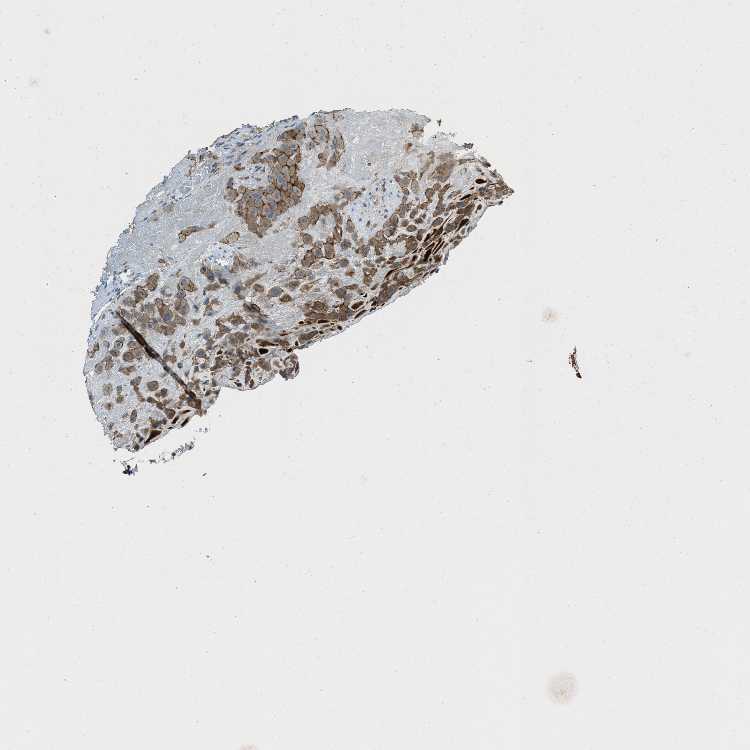

TISSUE PRIMARY DATA PLACENTA Show tissue menu

PLACENTA - Antibody stainingi

Antibody staining in the annotated cell types in the current human tissue is reported as not detected, low, medium, or high, based on conventional immunohistochemistry profiling in selected tissues. This score is based on the combination of the staining intensity and fraction of stained cells.

Each image is clickable and will lead to virtual microscopy that enables deeper exploration of all samples and also displays staining intensity scores, fraction scores and subcellular localization as well as patient and tissue information for each sample.

Antibody HPA020095Antibody HPA020138Antibody CAB010878Antibody CAB080402

Decidual cells MediumMedium-Medium

Trophoblastic cells HighMediumLowNot detected